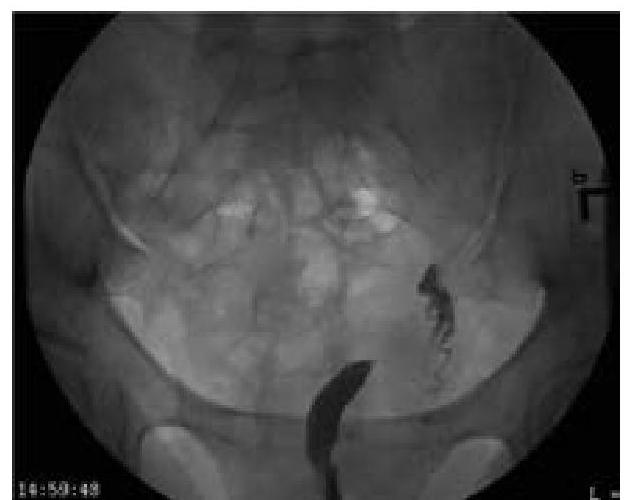

In a woman complaining of AUB following image was seen in endoscopic examination of uterus. What will be the diagnosis?

Explanation: ***Leiomyoma*** - The image shows **well-circumscribed, smooth, rounded masses protruding into the uterine cavity**, which are characteristic of **submucous (intracavitary) leiomyomas (fibroids)** seen on hysteroscopy. - Submucous leiomyomas are benign smooth muscle tumors that project into the endometrial cavity and commonly cause **abnormal uterine bleeding (AUB)** due to increased endometrial surface area, distortion of the endometrial cavity, ulceration of overlying endometrium, and interference with normal uterine contractility. - On **hysteroscopic examination**, they appear as firm, pale, smooth-surfaced masses with overlying endometrium. *Adenomyosis* - Adenomyosis involves the presence of **endometrial tissue within the myometrium**, leading to diffuse uterine enlargement. - On hysteroscopy, it may show a **globally irregular endometrial surface** with small endometrial openings or cystic spaces, but not the discrete, well-circumscribed protruding masses seen in the image. - While it can cause AUB and dysmenorrhea, the appearance is distinctly different from submucous leiomyomas. *Ovarian neoplasm* - Ovarian neoplasms originate in the **ovaries**, which are separate from the uterus. - **Hysteroscopic examination** visualizes only the **endometrial cavity** and cannot directly visualize ovarian pathology. - Ovarian masses do not protrude into the uterine cavity. *Carcinoma of uterus* - Endometrial carcinoma typically presents on hysteroscopy as **irregular, friable, ulcerative, or fungating lesions** with abnormal vascularity and易出血 (easy bleeding). - The **smooth, well-defined, and rounded appearance** with intact overlying mucosa in the image is characteristic of benign leiomyomas, not malignant growths. - Uterine sarcomas are rare and would show more irregular, infiltrative features rather than well-circumscribed masses.